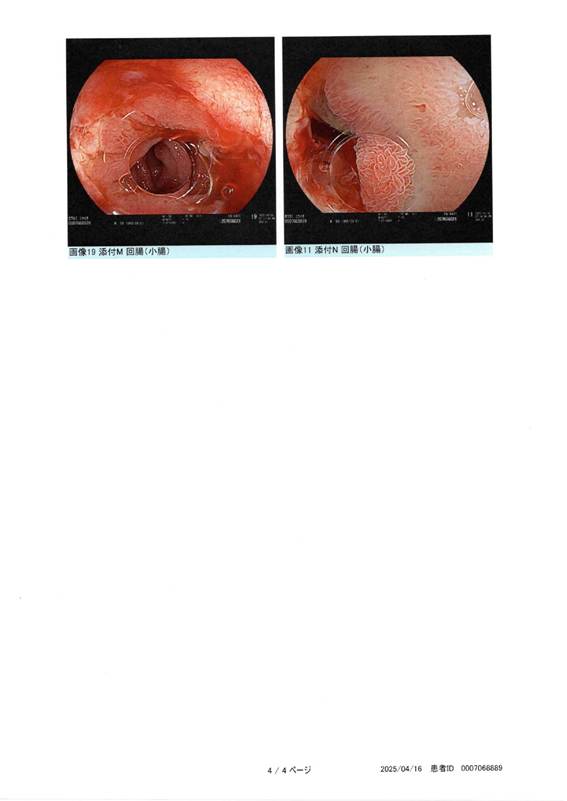

内視鏡写真

それからは「どうだったんだろう?」と気をもみながら横になっていると加治先生が来られて「最初やっぱり狭くなっていてカメラが通らなくて、拡張して通るようになりました。浅い潰瘍があったのでそれが治って瘢痕化して狭くなっていると思われる。そこ以外には特に潰瘍はありませんでした」と説明された。「便が少し赤みがかっていたんですが」と話を向けると「拡張時に処置しているのでその時の出血でしょうから、その後出血がなければ大丈夫です。」とのこと。明日は不在なので別の先生に経過観察をお願いしていて、食事ができて出血もなければ退院と告げられた。

19:00頃にも高津先生が来られて写真を見せてもらいながら同じような説明があった。

【説明内容】

・今回も前回と同じ吻合部に狭窄があり、(前回と同じ)4mm程度しか隙間がなかったのでカメラが通らなかった。

・ここをバルーンで拡張して12mmまで拡げた。

・今回もジワーッと出血したので、排便時に出血がないか注意してください。

・ヒュミラは効いているし、炎症反応も落ち着いているけど、吻合部はどうしても血流が悪いのでこうなりやすい。

・前回から半年でまた狭窄しているので、今後も半年に1回ペースでの拡張を考えた方が良い。